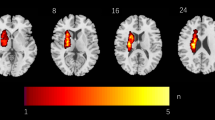

Due to its recent introduction, the adoption of white matter functional connectivity to probe the functional architecture of the brain is still controversial. For this reason, we performed a series of validation analyses to corroborate the integration of subcortical DES mapping with white matter resting state fMRI (Fig. 1). To provide a link between white matter hemodynamic fluctuations and underlying neural activity, we compared the spatial organization of white matter functional networks with the spatial organization of white matter metabolic networks as measured with [18F]-fluorodeoxyglucose functional positron emission tomography (FDG-fPET), a proxy for dynamic neural activity. The FDG-fPET dataset consisted of 26 healthy control subjects (77% female, 18–23 years old, N = 25 for the current study) scanned with a protocol that allows the tracking of metabolic oscillations similarly to resting state fMRI31,32. For each subject, we partitioned the white matter in 50 regions of interest using ICBM-DTI-81 white-matter labels atlas33 as provided by FSL, extracting region-averaged time series from both the FDG-fPET and resting state fMRI datasets using nilearn (v0.10.034). We then transformed Pearson’s r scores to z scores using Fisher’s r-to-z transform, and we finally obtained metabolic and functional connectivity at the group level by averaging single subject matrices. Averaged matrices were converted back to Pearson’s r value via the tanh function (numpy v1.21.526). We assessed the degree of similarity in the spatial distribution of metabolic and functional connectivity in the white matter by correlating the two matrices row-wise, correcting for spatial autocorrelation using parametrized null models (10,000 instantiations per region with default parameters using the python implementation of BrainSMASH35) and multiple comparisons with a false discovery rate procedure (python package statsmodel v0.9.0)36. We removed 10 regions of interest for which the null model preserving spatial autocorrelation returned a non-optimal fit to the empirical data (Pearson’s r between one average null model and empirical data <0.75, 1000 null realizations, scipy v 1.7.3), as recently suggested37.

We used lesion network mapping to derive functional networks from the set of both DES cortical and subcortical points (rendered on the surfaces reconstruction of the gray and white matter, respectively), mapping functional network hubs in both white and gray matter in a normative sample of 1000 healthy individuals (see main text). We used functional hubs as waypoints for tractography filtering in an additional independent cohort of 753 healthy subjects, obtaining in a data driven manner function specific wiring diagrams that were segmented in a semi-automated manner to extract white matter pathways, and converted to a volumetric representation for the clinical analyses. We also probed the robustness and biological foundation of white matter DES-derived functional networks by comparing cerebral oxygenation dynamics and metabolic fluctuations in the white matter, as well as by investigating whether white matter DES-derived functional networks are predictive of unseen stimulation points. A.U arbitrary units, DES direct electrical stimulation, FC functional connectivity, FDG-fPET [18 F]-fluorodeoxyglucose functional positron emission tomography, GM gray matter, WM white matter.